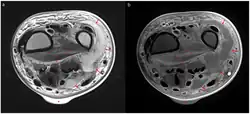

Magnetic resonance imaging (MRI)

Magnetic resonance imaging (MRI) is considered superior to computed tomography (CT) in the visualization of soft tissues and is able to detect about 93% of NF cases.[15] It is especially useful in finding fluid in the deep fascia, which can distinguish between NF and cellulitis.[15] When fluid collects in the deep fascia, or thickening or enhancement with contrast, necrotizing fasciitis should be strongly suspected. However, MRI is much slower than CT and not as widely available.[15] There may also be limitations on its use in patients with kidney problems.[15]